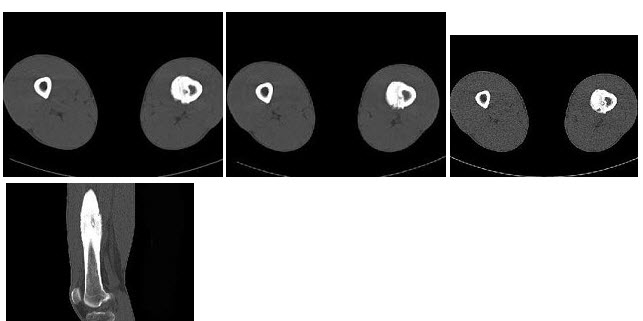

59、多项选择题

女,6个月,CT扫描如图所示,下列说法正确的是()

A.双侧肾盂积水

B.双侧肾门朝向前内方

C.双肾下极融合

D.考虑为异位肾

E.考虑为马蹄肾

60、单项选择题 下列实现数字化最迟的是哪项技术()